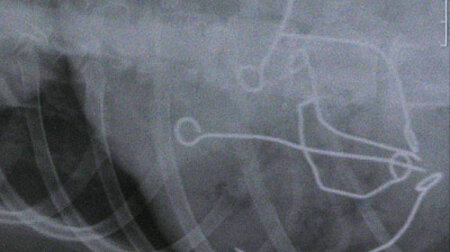

Dort angekommen, zeigten sich im Röntgenbild tatsächlich sechs, teilweise völlig verbogene, zerkaute Metallspieße. Nach Aufklärung seitens der Klinik über die Risiken dieses Notfalles, vor allem in Bezug auf die Fremdkörper und die Narkoserisiken, wurde eine Endoskopie unter Vollnarkose angeschlossen.

Die Spieße waren im Magen frei beweglich und nirgends in die Magenwand eingespießt, sodass die Endoskopie einigermaßen komplikationslos verlief. Alle sechs Spießchen erblickten nacheinander wieder das Tageslicht. Eine langwierige Operation mit eröffnetem Bauch blieb dem Hund deshalb zum Glück erspart. Nachdem er seinen Rausch von der Narkose ausgeschlafen hatte, konnte der Rüde wieder gesund entlassen werden.